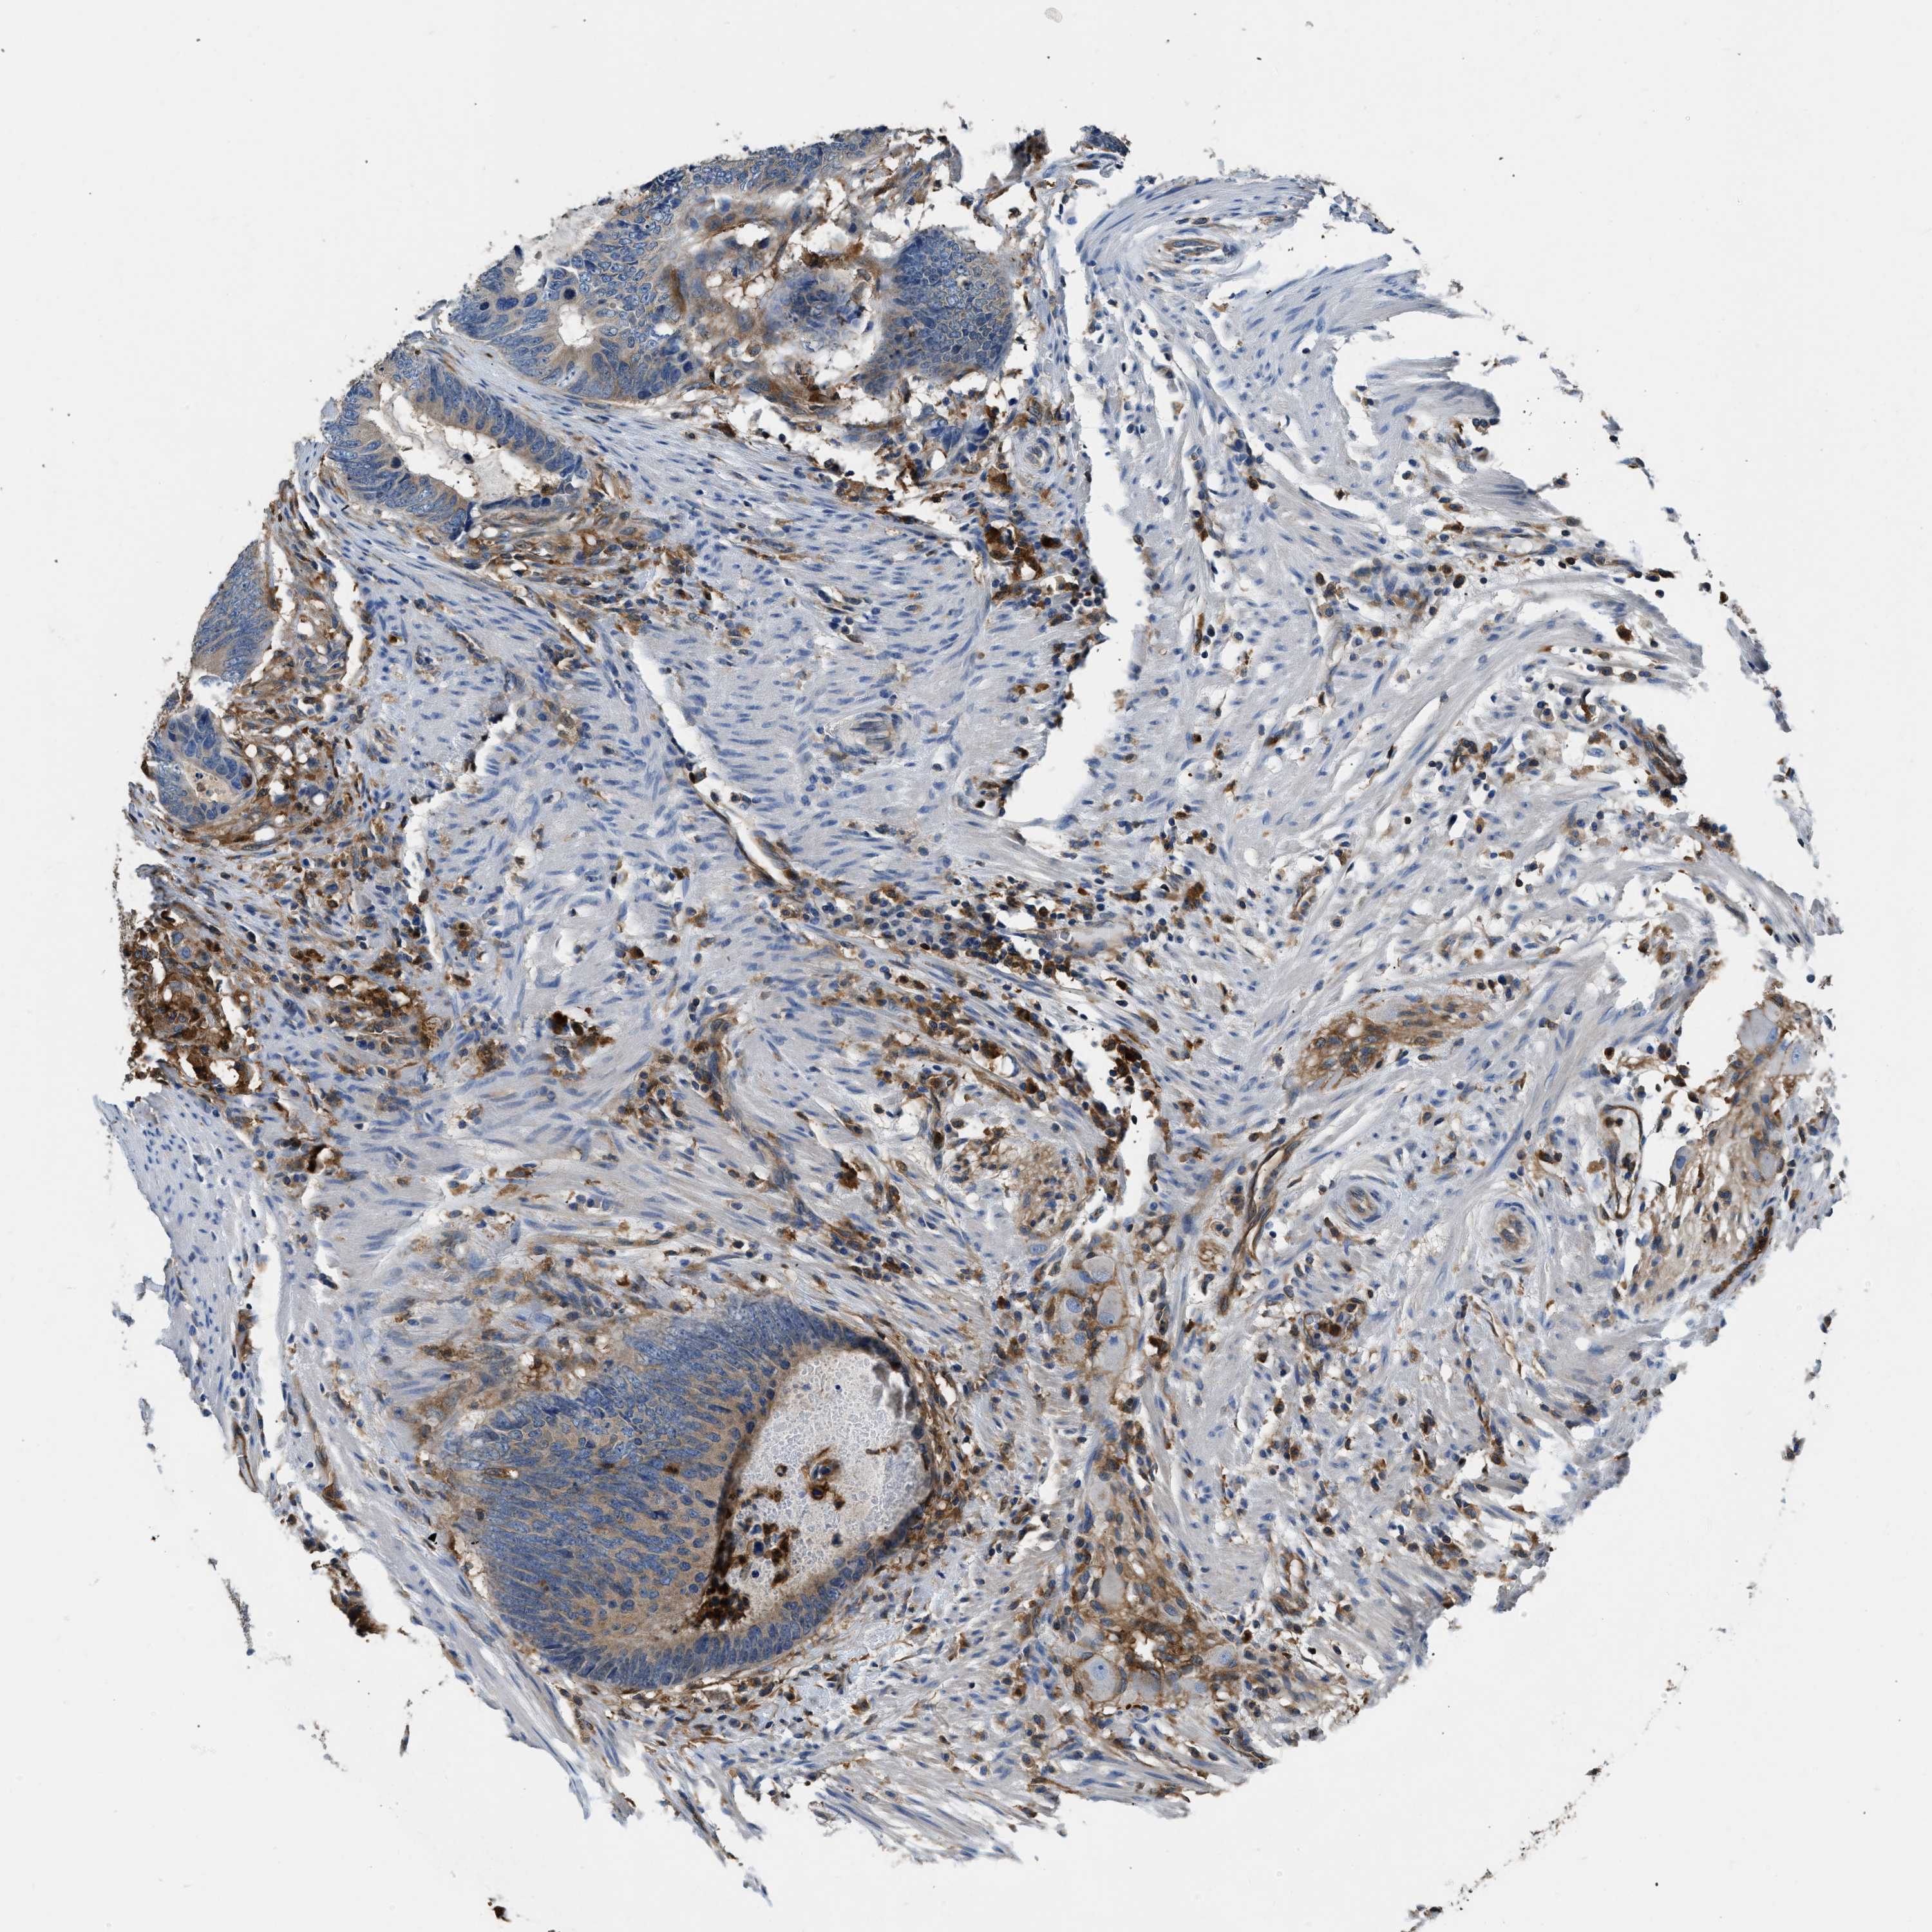

CANCER COLORECTAL CANCER Show tissue menu

Colorectal cancer

Human cancer

Colon adenocarcinoma